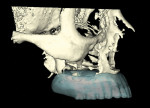

Ten radiopaque markers (gutta percha, Hygenic®, Coltène/Whaledent Group, www.coltene.com) were placed in the maxillary complete denture to prepare the denture for a specific guided- surgery protocol (NobelClinician™ Software, Nobel Biocare USA, LLC, www.nobelbiocare.com).23-30 This protocol uses a dual cone beam computed tomography (CBCT) scan procedure. The first CBCT scan (i-CAT®, Imaging Sciences International Inc., www.imagingsciences.com) was taken with the patient’s dentures in place, and a second CBCT scan was taken of the maxillary complete denture alone. The two scans were exported in Digital Imaging and Communications in Medicine (DICOM) format and loaded into the guided-surgery software, where a 3-dimensional (3-D) virtual working model of the patient was generated (Figure 4 through Figure 7) to enable virtual implant planning to be performed. Because the patient’s denture contained the approved esthetic arrangement of the teeth, the implants could be placed virtually in the most prosthetically favorable position.

A copy of the first CBCT scan was sent to an oral maxillofacial radiologist, and accomprehensive radiology report was generated. The findings were as follows: There was pneumatization of the great wing and pterygoid plates of the left sphenoid sinus, and severe atrophy was noted in both the maxillary and mandibular alveolar processes.